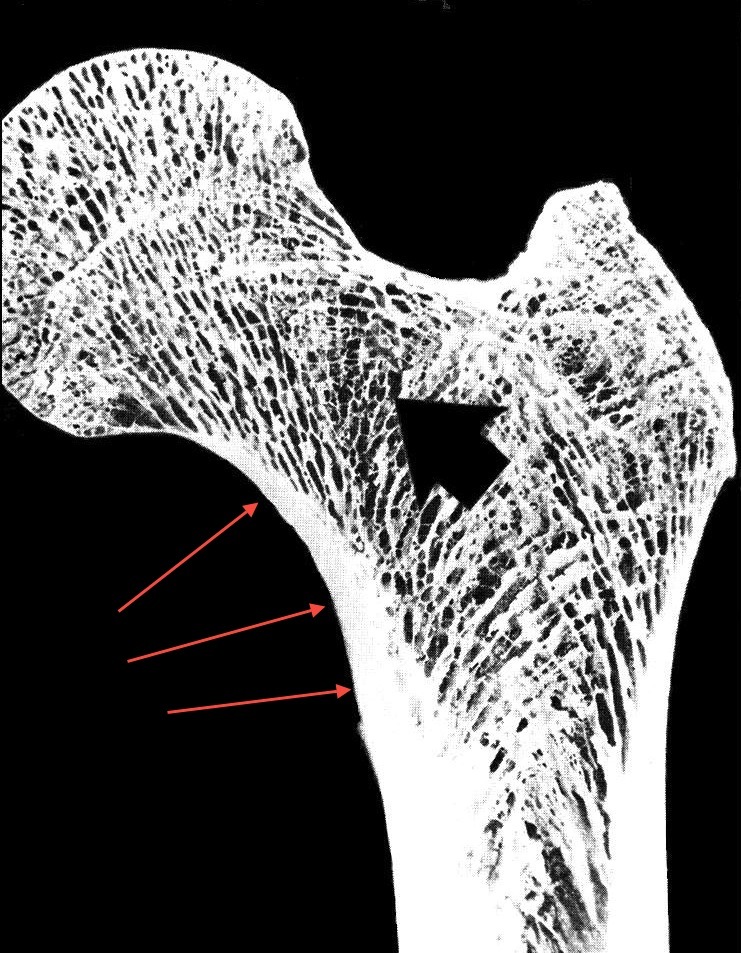

Identify the osteoblasts in this woven bone